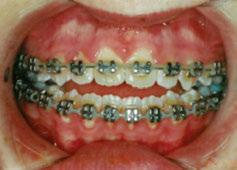

This case involves a 13-year-old female patient with a complex malocclusion that includes multiple dental and skeletal issues. During the initial consultation, clinical evaluation showed severe maxillary crowding along with generalized spacing in the mandibular arch. The patient’s occlusal relationships were asymmetric, with a Class I molar relationship on the right side and a Class II molar relationship on the left. Notably, an anterior crossbite was observed, further complicated by a narrow, V-shaped maxillary arch — a common presentation that often exacerbates anterior-posterior discrepancies and limits functional occlusion. The patient also demonstrated poor oral hygiene, which is a key indicator of an indirect bonding system that does not reduce excess flash. ODB is superior in flash reduction, by being able to remove excess adhesive from three sides of the bracket instead of competitors who only remove adhesive from one side of the bracket. The presence of adhesive around brackets contributes to surface roughness which leads to plaque accumulation.1 Flash reduction will be very important for every patient’s orthodontic success (Figures 1-3).

The initial bonding appointment was completed efficiently within 35 minutes, including a comprehensive session on oral hygiene instructions and home care practices. Efficient time management at this visit allowed for strong patient education and engagement, factors that contributed positively to overall treatment adherence and outcomes.

The treatment spanned a total of 12 appointments, which included all routine, emergency, and one reposition appointment. Notably, the reposition was necessitated by a clinician error in the delivery of a bonding jig, resulting in bracket misplacement. This underscores the technique sensitivity involved in indirect bonding systems and highlights the importance of clinician training and procedural verification. Emphasis on consistent technique evaluation and training among providers has proven instrumental in reducing such avoidable errors (Figures 4-6).